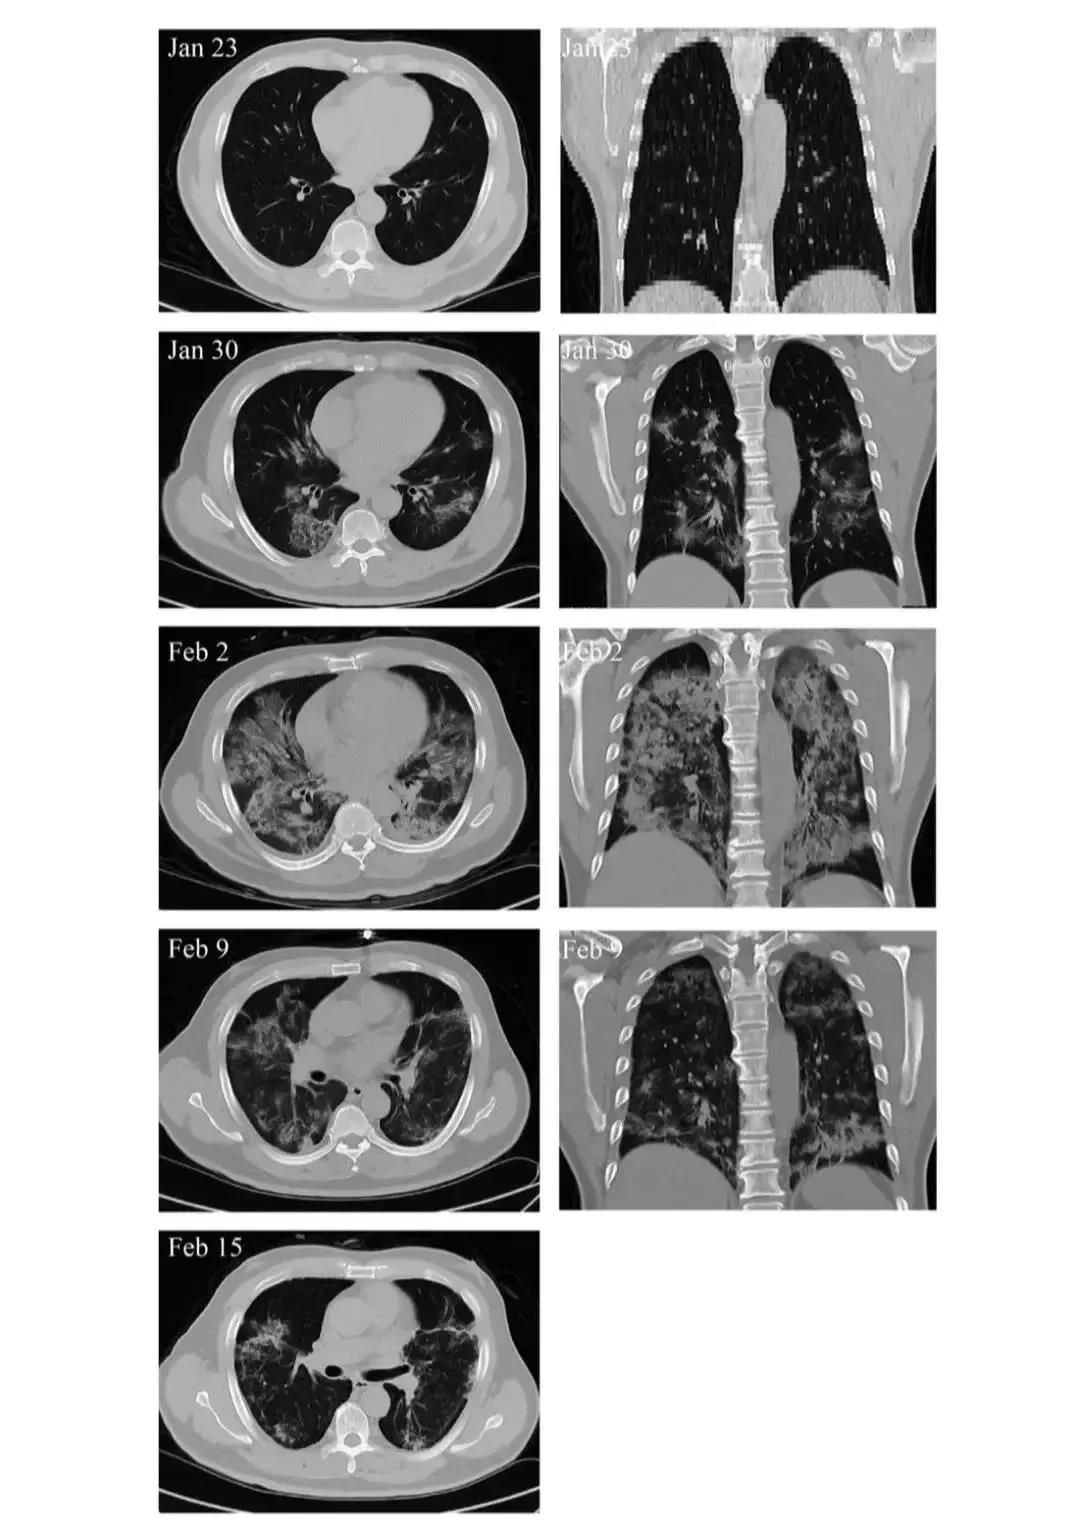

间充质干细胞移植有效阻止免疫系统对器官的攻击。2月1日,患者血浆天冬氨酸转氨酶、肌酸激酶活性和肌红蛋白分别激增至57 U/L、513 U/L和138 ng/ml,表明肝脏和心脏遭受严重损害;但这些功能性生化指标的水平均在移植后2〜4天降至正常参考值,2月13日恢复至正常水平,分别为19 U/L,40 U/L和43 ng/ml。另外,MSC移植能显著加快治疗进程。移植后4天,新冠肺炎危重症患者呼吸频率降至正常范围、发烧和呼吸急促等症状消失。移植后9天,胸部CT成像显示毛玻璃样混浊和肺炎浸润已大大减少。

危重患者肺部影像学显示症状改善